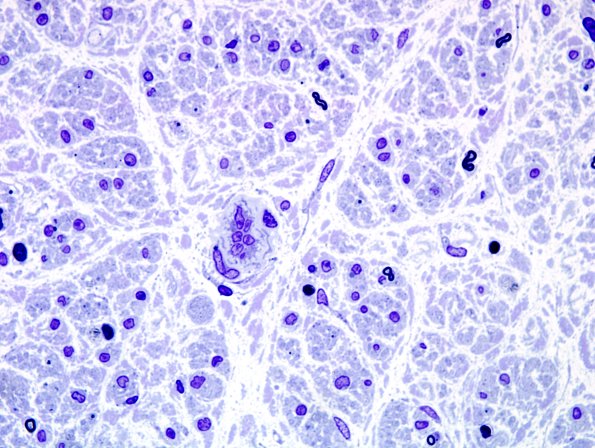

Washington University Experience | PERIPHERAL NEUROPATHY | 4 AXONAL DEGENERATION | 2 Plastic Sections | 14A2 Axonal degeneration (end-stage nerve, Case 14) Plastic 1

There are only a few small myelinated axons remaining in this fascicle.